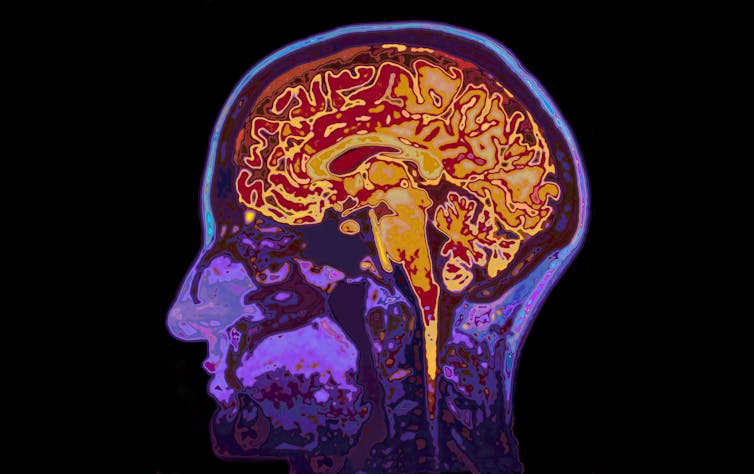

The lonely brain

When we spend quality time with another person, we experience intrinsic joy. Brain scanning studies show that subcortical brain regions, such as the ventral striatum, which plays an important role in motivation, are activated when receiving monetary and social rewards.

When we feel lonely and rejected, brain regions associated with distress and rumination are activated instead. This may be due to evolution driving us to establish and maintain social connections to ensure survival. Lonely people also have a more negative focus and anxiously scrutinize people’s intentions. Sometimes this can become so strong that it makes us feel even more lonely – creating a vicious cycle.